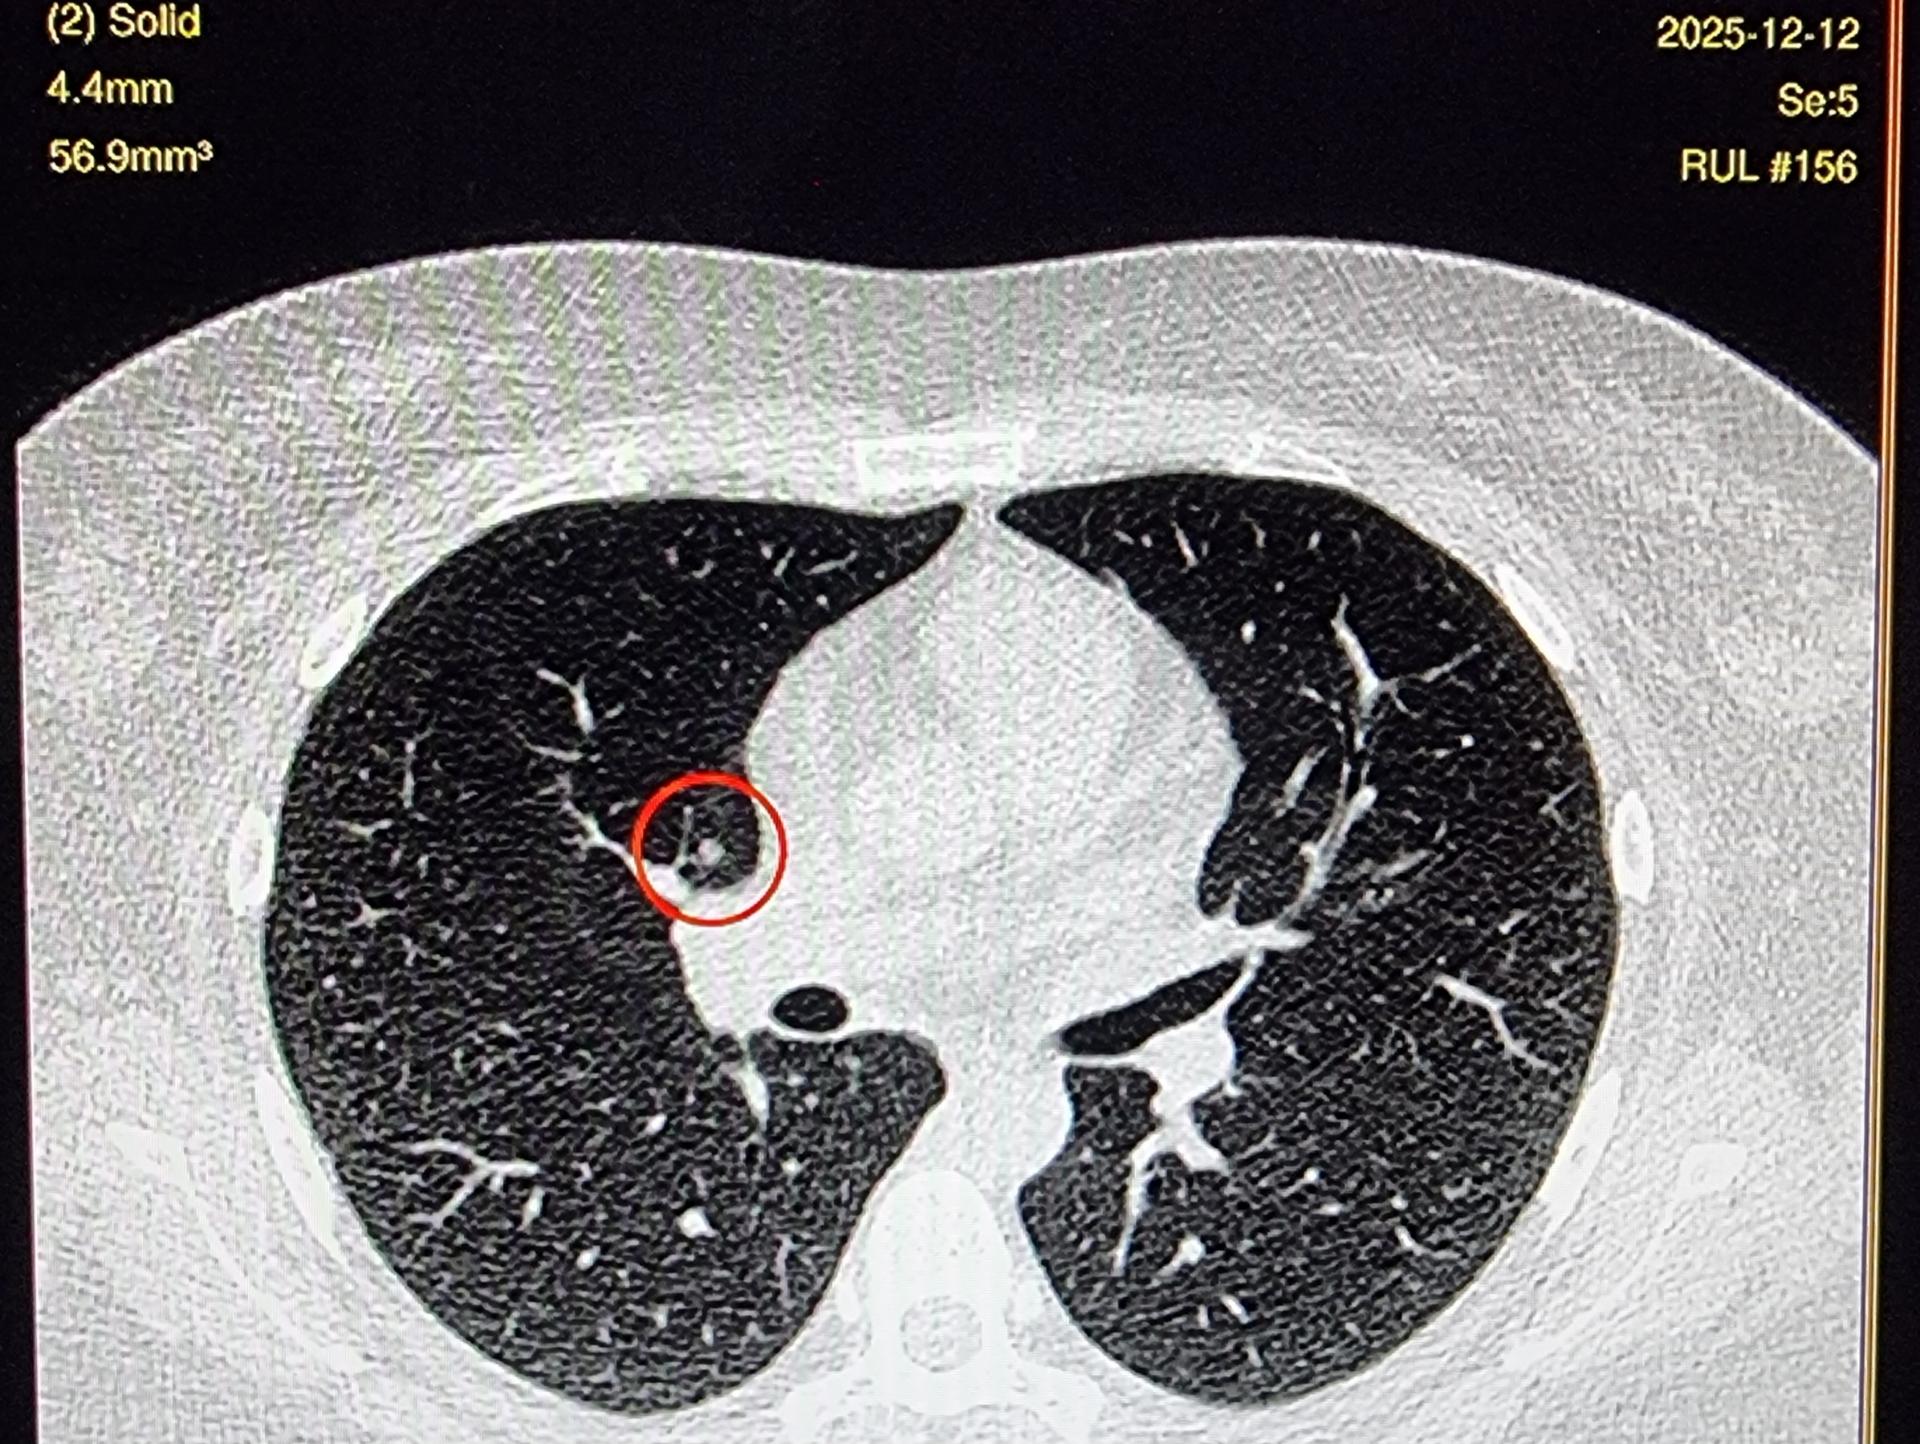

저선량 폐CT 영상보는데 이게 뭔가요? luCAS-plus

제 폐CT영상 잘받았나 확인하는데 끝에

이런게 있어요. luCAS-plus 항목에요.

오늘 의사에게도 우상엽 결절 못들었어요

오히려 추적하던 고형결절 안보인다고 오지말라고 진료종료났ㅇㅓ요

판독의가 쓴 판독지에서도 내용없어요.

결절 맞나요

결절의 크기가 작은 것 같습니다.

CT에서 환자분이 말씀하신 것처럼 작은 결절은 한 커트만으로는 알 수 없고 여러 커트를 봐야 합니다.

그런데 이상하네요 다른건 몰라도 4.4mm 라고 되어 있는 것은 크기를 측정한 것 같은데 말이죠..

어찌되었던 이 사진만 보면 결절처럼 보이기는 합니다.

하지만 결절은 위아래 사진을 같이 확인을 해보셔야 합니다.

한 커트에만 나와있다면 약간 애매하다 할 수 있습니다.

말씀하시는 결절이 착오가 아니라고 하더라도 모양이나 크기로 봐서는 추적관찰을 하면 되는 것처럼 보입니다.

이는 담당선생님과 확인을 해보세요

이전 진료에서 이 결절에 대한 이야기를 못 들었는데 다시 확인을 해달라고 해보세요